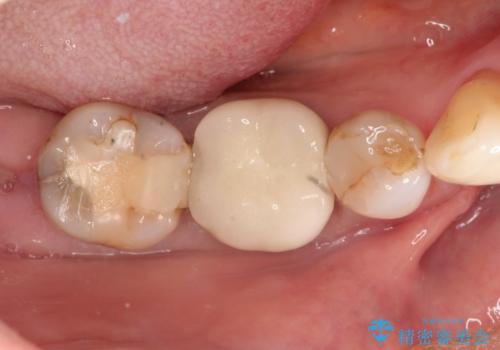

虫歯の治療 オールセラミッククラウン

- 他院にて以前治療した修復物の下に虫歯を認めたため、オールセラミックにて修復治療を行なっております。

オールセラミッククラウンは天然歯と同様に透明感を出すことができ、より審美的な治療が可能です。